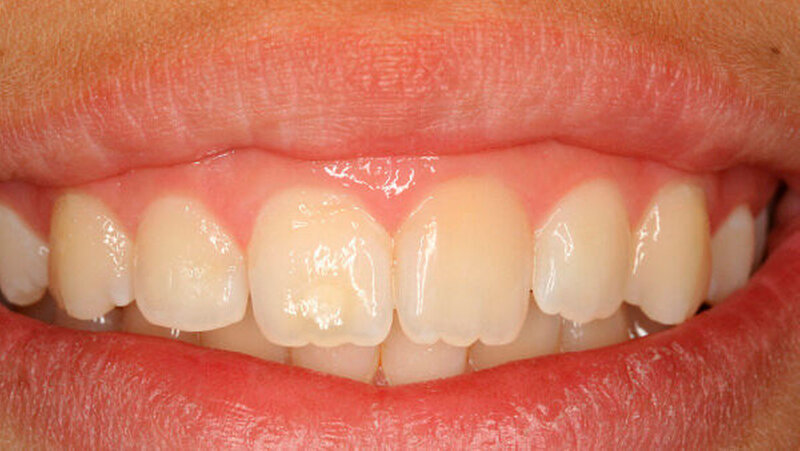

An Zahn 11 zeigte sich im inzisalen Drittel zusätzlich eine runde Schmelzopazität mit geringfügiger Hypoplasie (Abbildung 3), beides waren die Folge eines Frontzahntraumas im Milchgebiss. Darüber hinaus befand sich im zervikalen Drittel des gleichen Zahns eine rillenförmige Hypoplasie im Schmelz, höchstwahrscheinlich durch denselben Unfall verursacht (Abbildung 3).